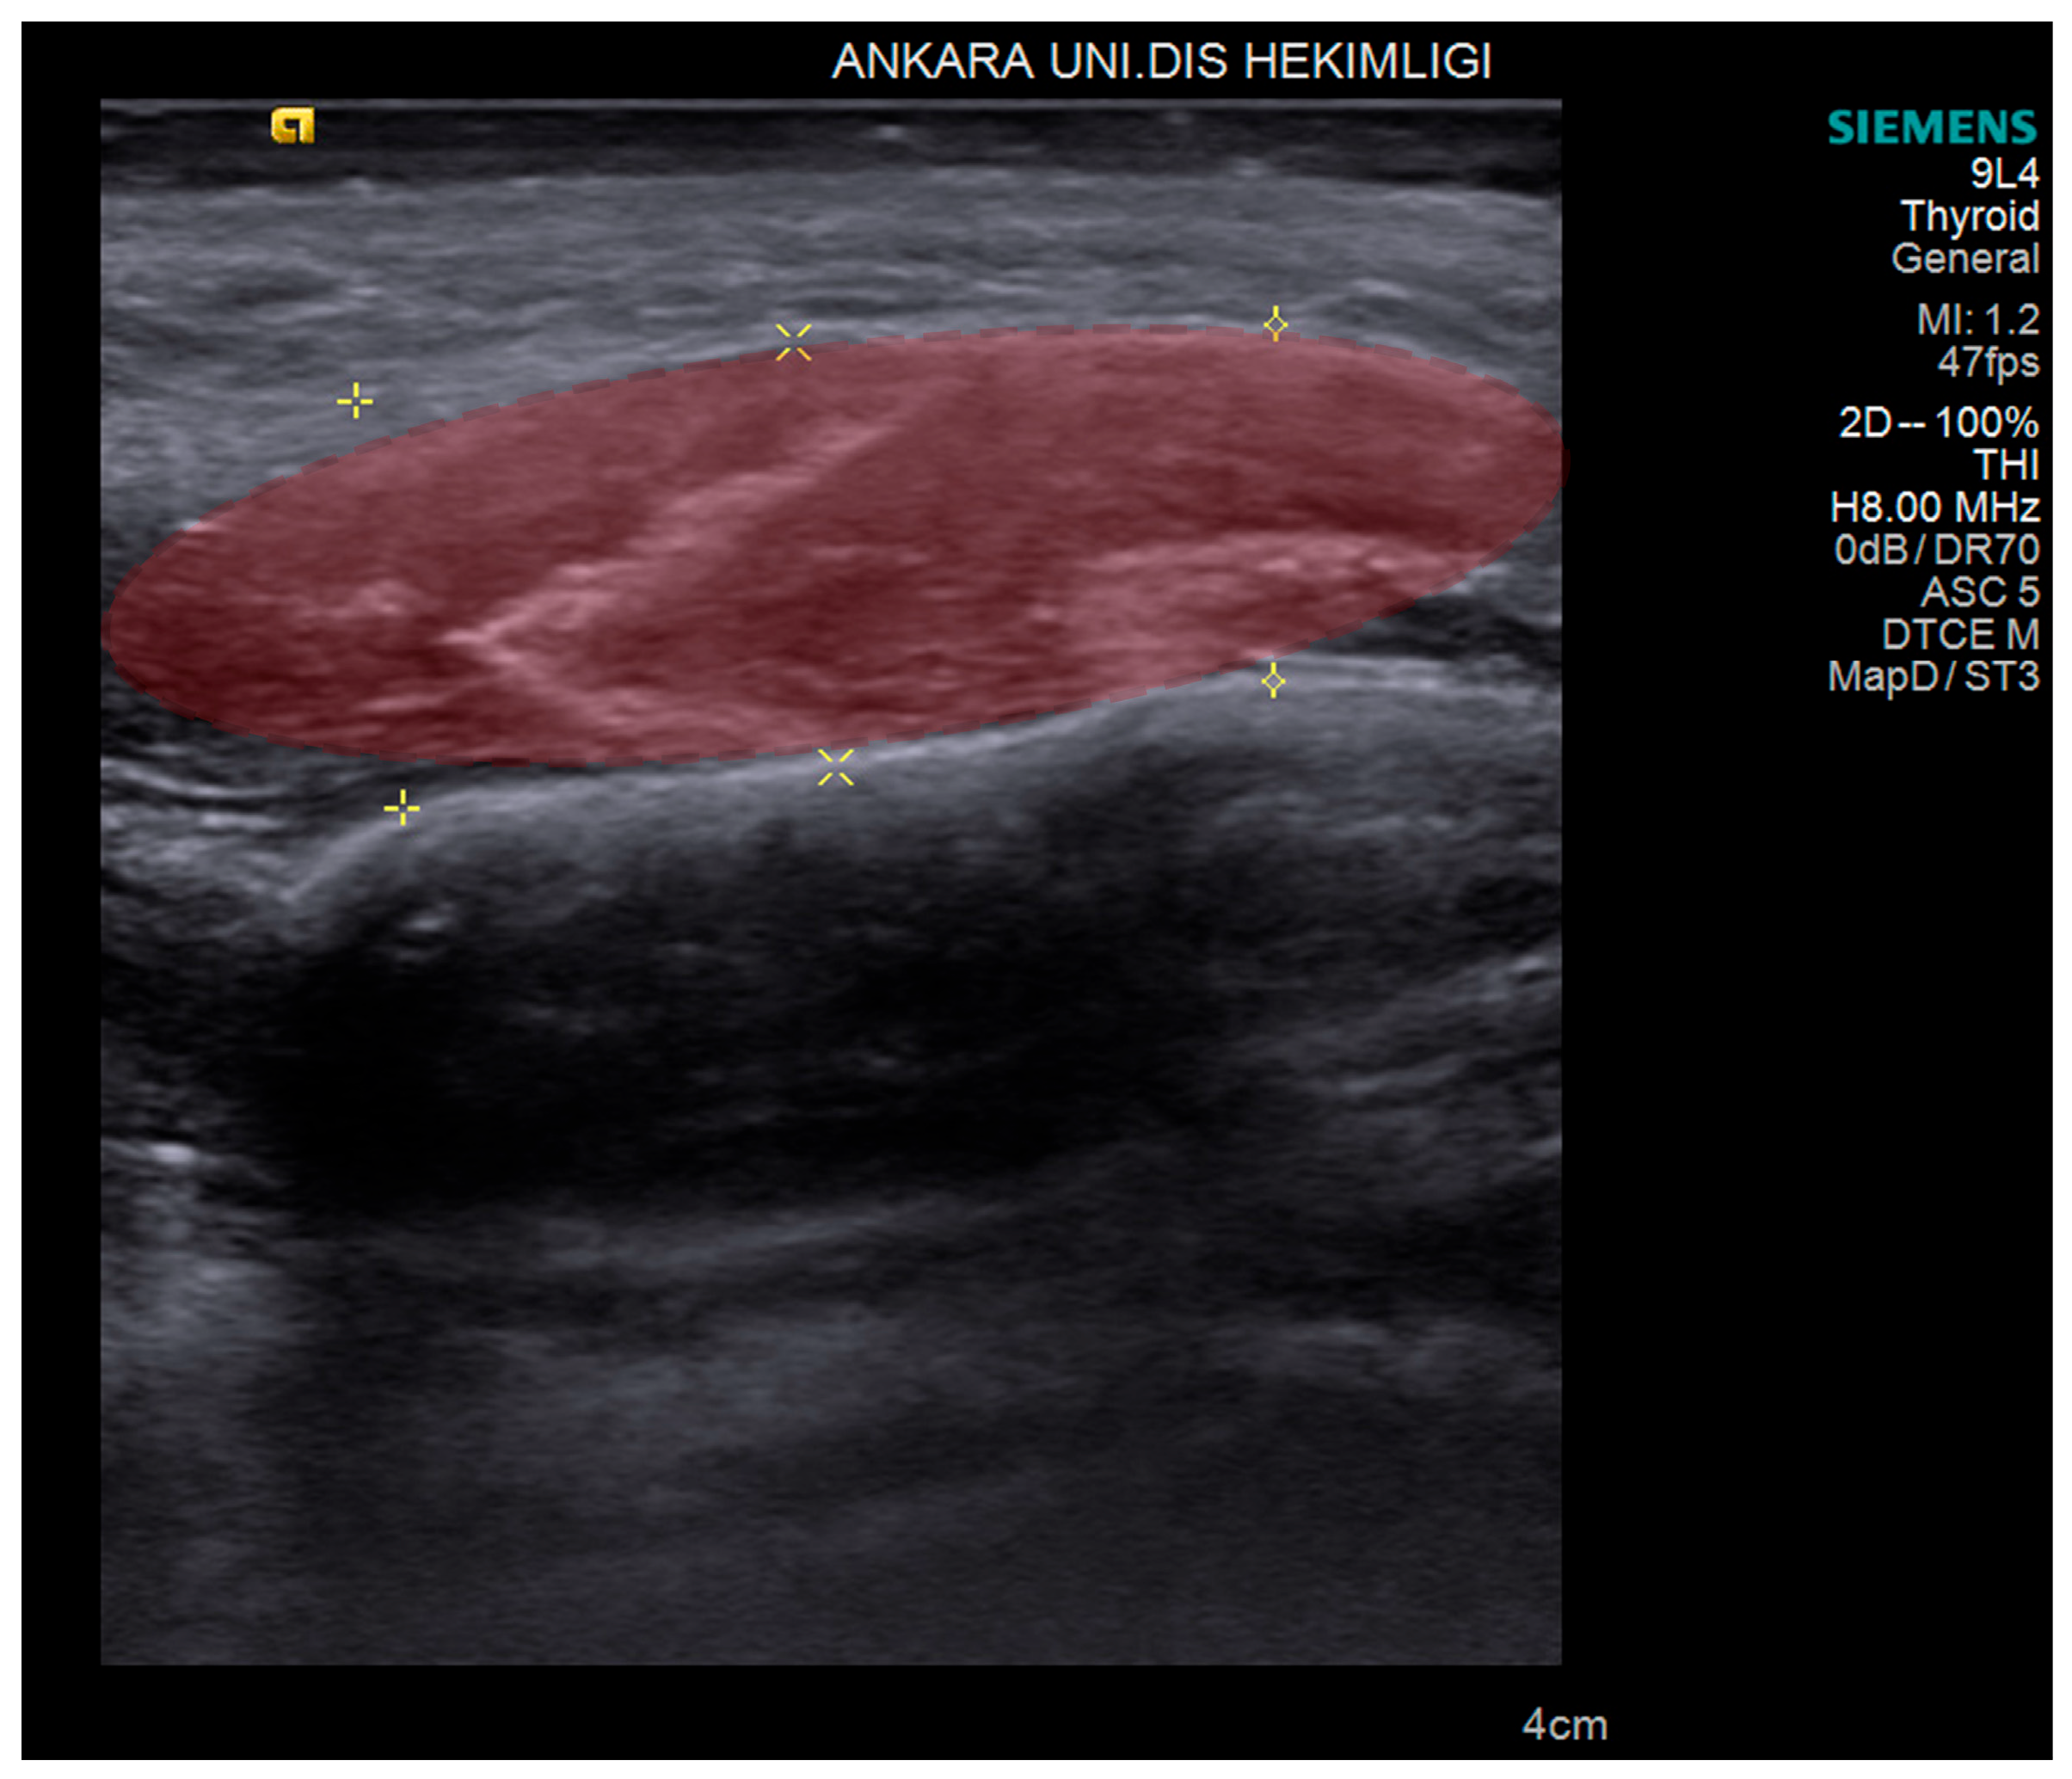

2.2. USG Imaging

2.3. USG Image Segmentation